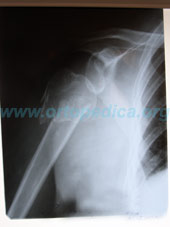

Рентгенограмма до операции

Рентгенограмма оскольчатого перелома плеча